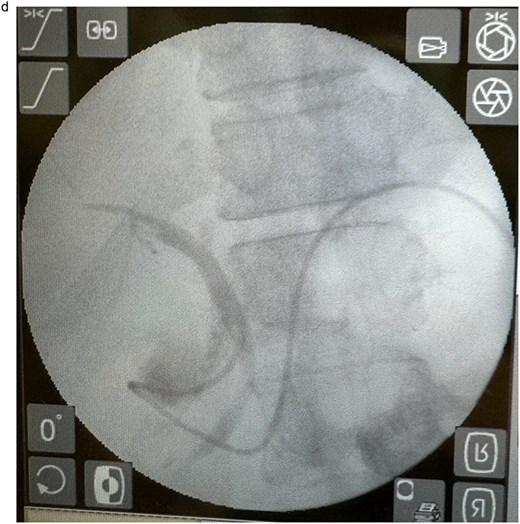

In view of the ongoing leakage and the hostile operative field, a third intervention was undertaken on postoperative day 24 following the second surgery. After multidisciplinary discussion, a combined surgical–endoscopic approach was undertaken in collaboration with internal medicine specialists. Intraoperative findings revealed dense adhesions from prior surgeries and a 0.5-cm perforation at the proximal duodenal stump, located near the ampulla of Vater. Initial endoscopic retrograde cholangiopancreatography (ERCP) was unsuccessful due to limited ampullary access; thus, EUS-CDS with ENBD placement was performed as an alternative strategy. From the duodenal bulb, the common bile duct (CBD) measured 4.7 mm on EUS, and Doppler confirmed no intervening vessels (Figs 4a and 4b). A 19-gauge EZ Shot 3 needle (Olympus) was used to puncture the extrahepatic bile duct, and bile aspiration followed by contrast injection confirmed correct positioning (Fig. 4c). A VisiGlide 2 angled guidewire (0.025 inch) was advanced into the right intrahepatic duct, and the tract was dilated using an ES dilator. A 7-Fr ENBD catheter was subsequently deployed across the choledochoduodenostomy under fluoroscopic guidance, achieving effective biliary drainage (Figs 4d and 4e). In addition, a 16-Fr Foley catheter was inserted into the duodenal perforation as a duodenostomy tube (Fig. 4f) for external drainage, and six closed wound vacuum drains were placed for peritoneal irrigation and drainage.

Endoscopic image demonstrating the 7-Fr ENBD catheter, with concurrent visualization of the duodenostomy tube at the proximal duodenal stump.

This combined approach achieved effective biliary diversion and clinical improvement. Total biliary drainage, including duodenostomy and ENBD output, stabilized at ~500 ml/day. During this period, oral intake was gradually resumed, supplemented by jejunostomy feeding. Once biliary output plateaued and clinical stability was achieved, the ENBD catheter was removed 2 months later. All external drainage tubes, including the duodenostomy, were subsequently removed. The patient advanced to full oral intake, jejunostomy feeding was discontinued, and the tube was removed without complication. Recovery was uneventful, with restoration of bowel function. Postoperative CT (Fig. 5) confirmed an intact gastrointestinal tract without obstruction.